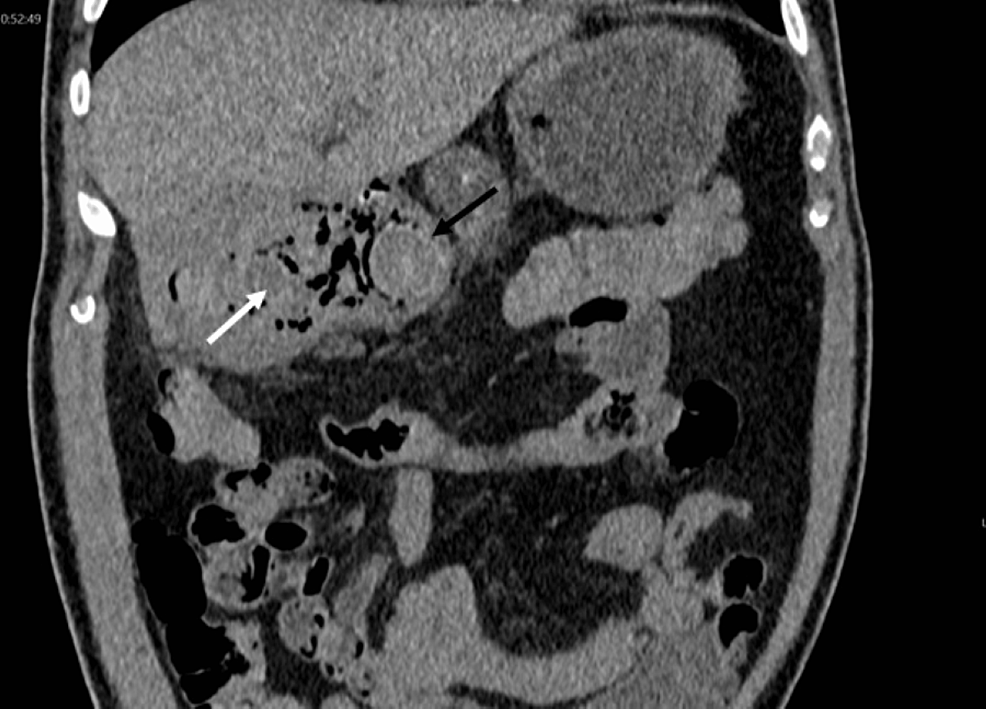

On day 3 of admission, he had further haematemesis (approximately 500 ml). He was transfused an additional unit of blood, started on tranexamic acid, and an inpatient oesophago-gastroduodenoscopy (OGD) was performed, which revealed that his stomach contained a large amount of blood and biliary stone material with clots occupying the pylorus and first section of the duodenum (D1). He was injected with 14 mililitre (mL) of adrenaline 1/10,000, then a hemostatic powder agent, haemospray, was used to achieve haemostasis. Haemospray is used endoscopically to produce an adhesive barrier with the bleeding site, and therefore, it forms a mechanical barrier to stop further bleeding. CT angiography was performed on the same day; it showed cholecystodoudenal fistula with stone eroding into D1 (Figures 1–2). The patient underwent endoscopic retrieval of the calculous and a naso-jejunal tube was placed for feeding. Subsequently, the patient made a steady recovery and was safely discharged home.